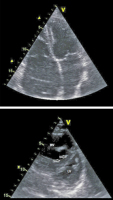

Rechtsherzdilatation

Abbildung 1: Durchmesser > 42 mm an der Rechtherzbasis, > 35 mm in der Ventrikelmitte werden als Rechtsherzdilatation gewertet, ebenso ein Längsdurchmesser > 86 mm.